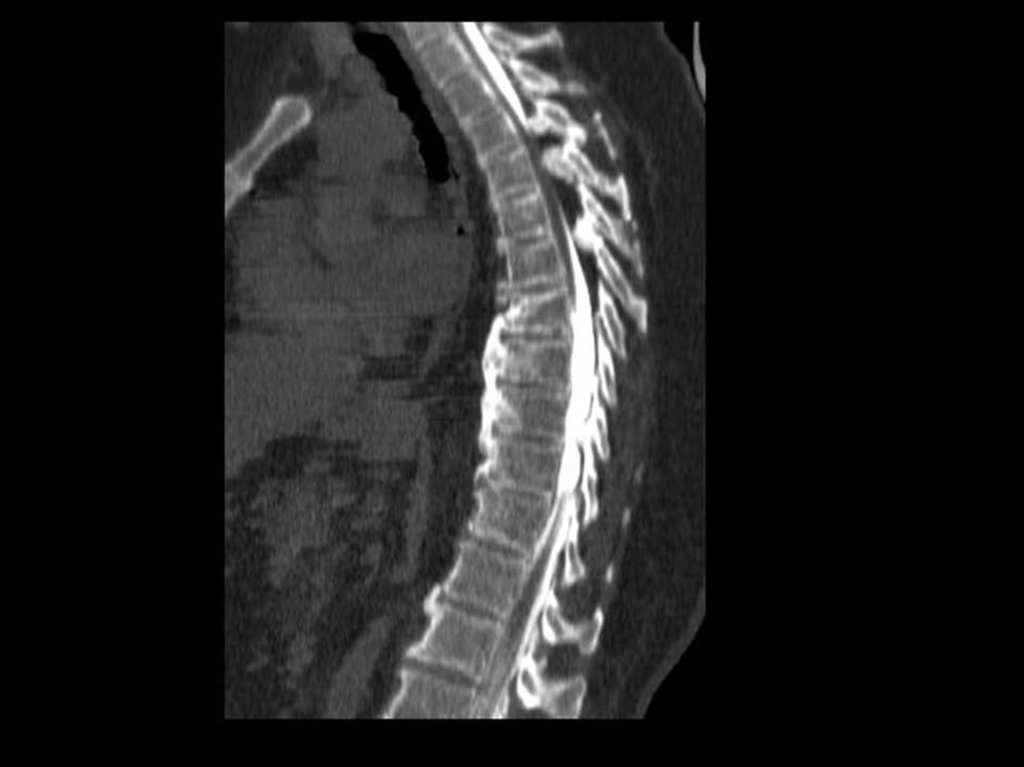

В грудном отделе – патология рёбернопозвонковых

суставов

с

формированием

артрозов. Поскольку грыжи выпадают в вогнутую

сторону, то в грудном отделе их наличие не

приводит к сдавлению спинного мозга.